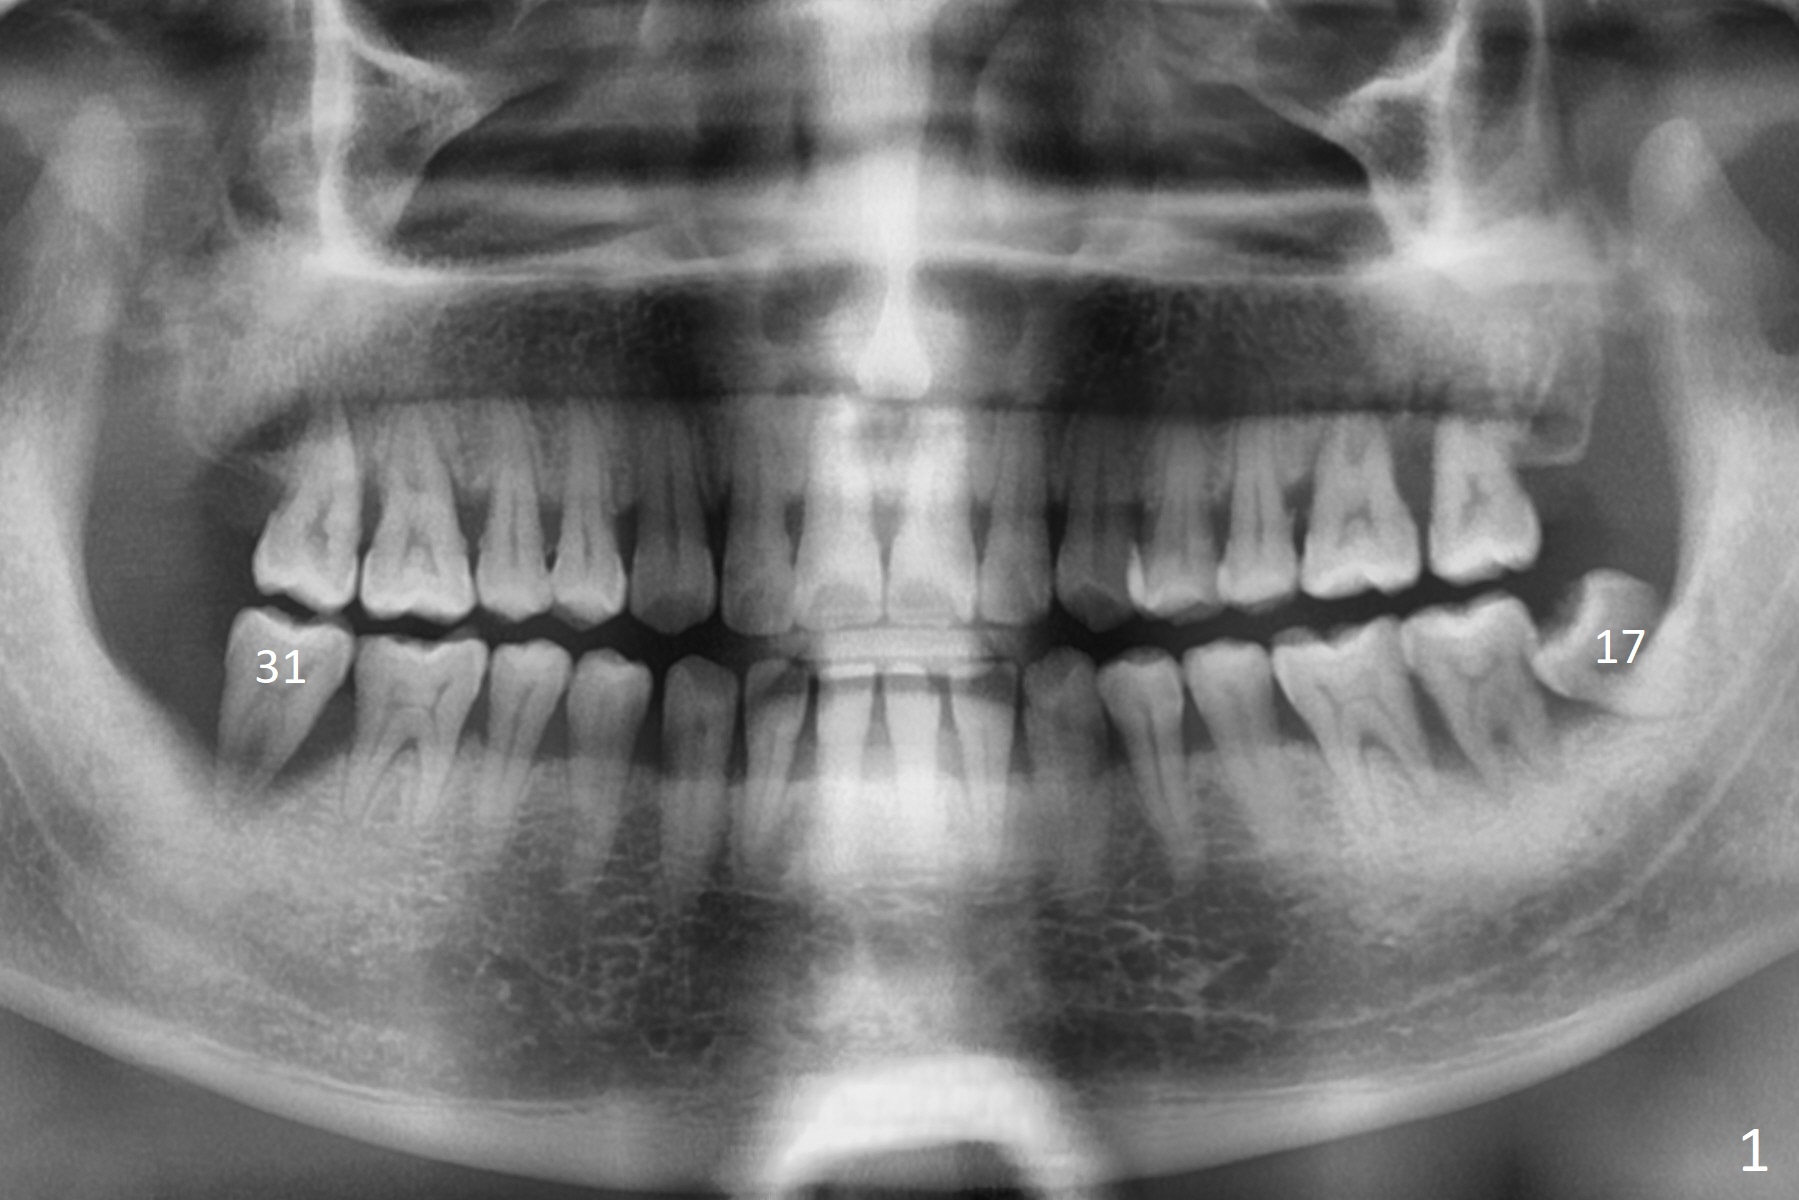

A 40-year-old man (smoker, 1ppd) is concerned about #31 mobility (Fig.1). Gross debridement is finished in his 1st appointment, while impression is taken for guide in his 2nd one. SRP has been scheduled for lower right quadrant with #31 extraction and immediate implant (Fig.2). The tooth #17 extraction will be postponed. The extraction may lead to mobility of the tooth #18, although SRP for the other 3 quadrant will be scheduled 1 week post #31 surgery. Smoke reduction is encouraged. When the crown is delivered at #31 one year later, the tooth #18 is loose (Fig.3) with lingual fistula. Since bone loss is more severe lingual (L *), a 5x10 mm immediate implant will be placed buccal (Fig.4). The tooth #17 will be kept as a distal stop for guide and extracted after #18 implant placement. Bone loss at #18 is more severe with mobility 15 months later; a shorter implant will be placed (Fig.5). After local scaling & root planing of the distal surface of #19 and application of Endogain, place sticky bone (red circle). Insert Collagen or Osteogen Plug in the #17 sockets.